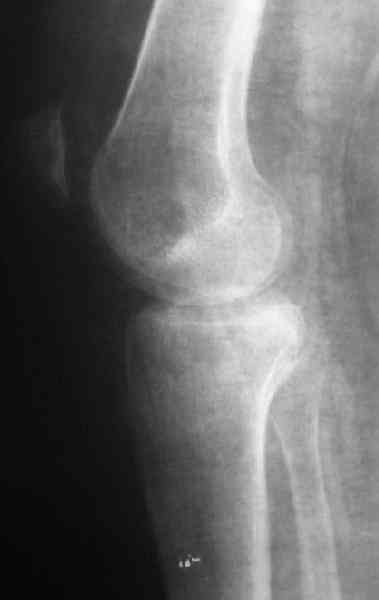

По тактике лечения, более импонирует второй вариант, но наружная плато расколота и туда при нагрузке внедряется н/мышелка бедра, поэтому после дистракции как репонирвать: или стяжными винтами, или изогнутами спицами или субхондральная костная пластика?

Недавно поступила больная через 1,5- 2 месяца.